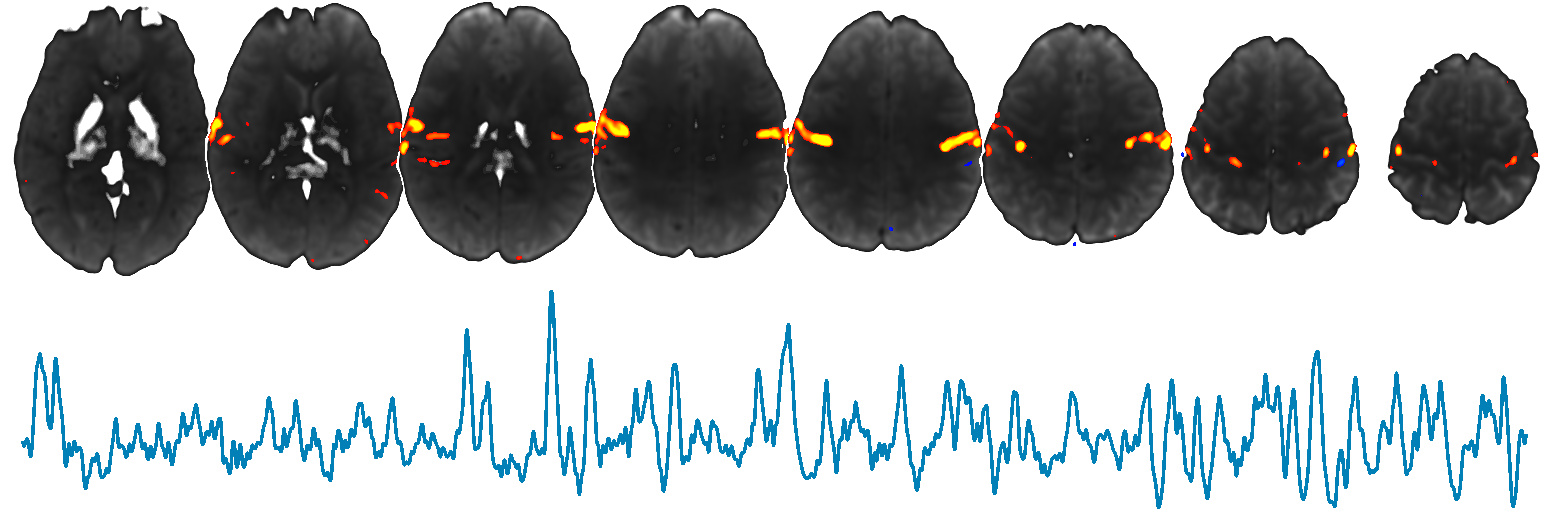

FIX is a tool which can be used to remove noise from 4D FMRI data. FIX is intended to be run on single-session MELODIC ICA output. FIX attempts to auto-classify ICA components into good vs bad components, so that the bad components can be removed from 4D FMRI data. See example raw data movies showing the (potentially huge) effect of FIX cleanup.